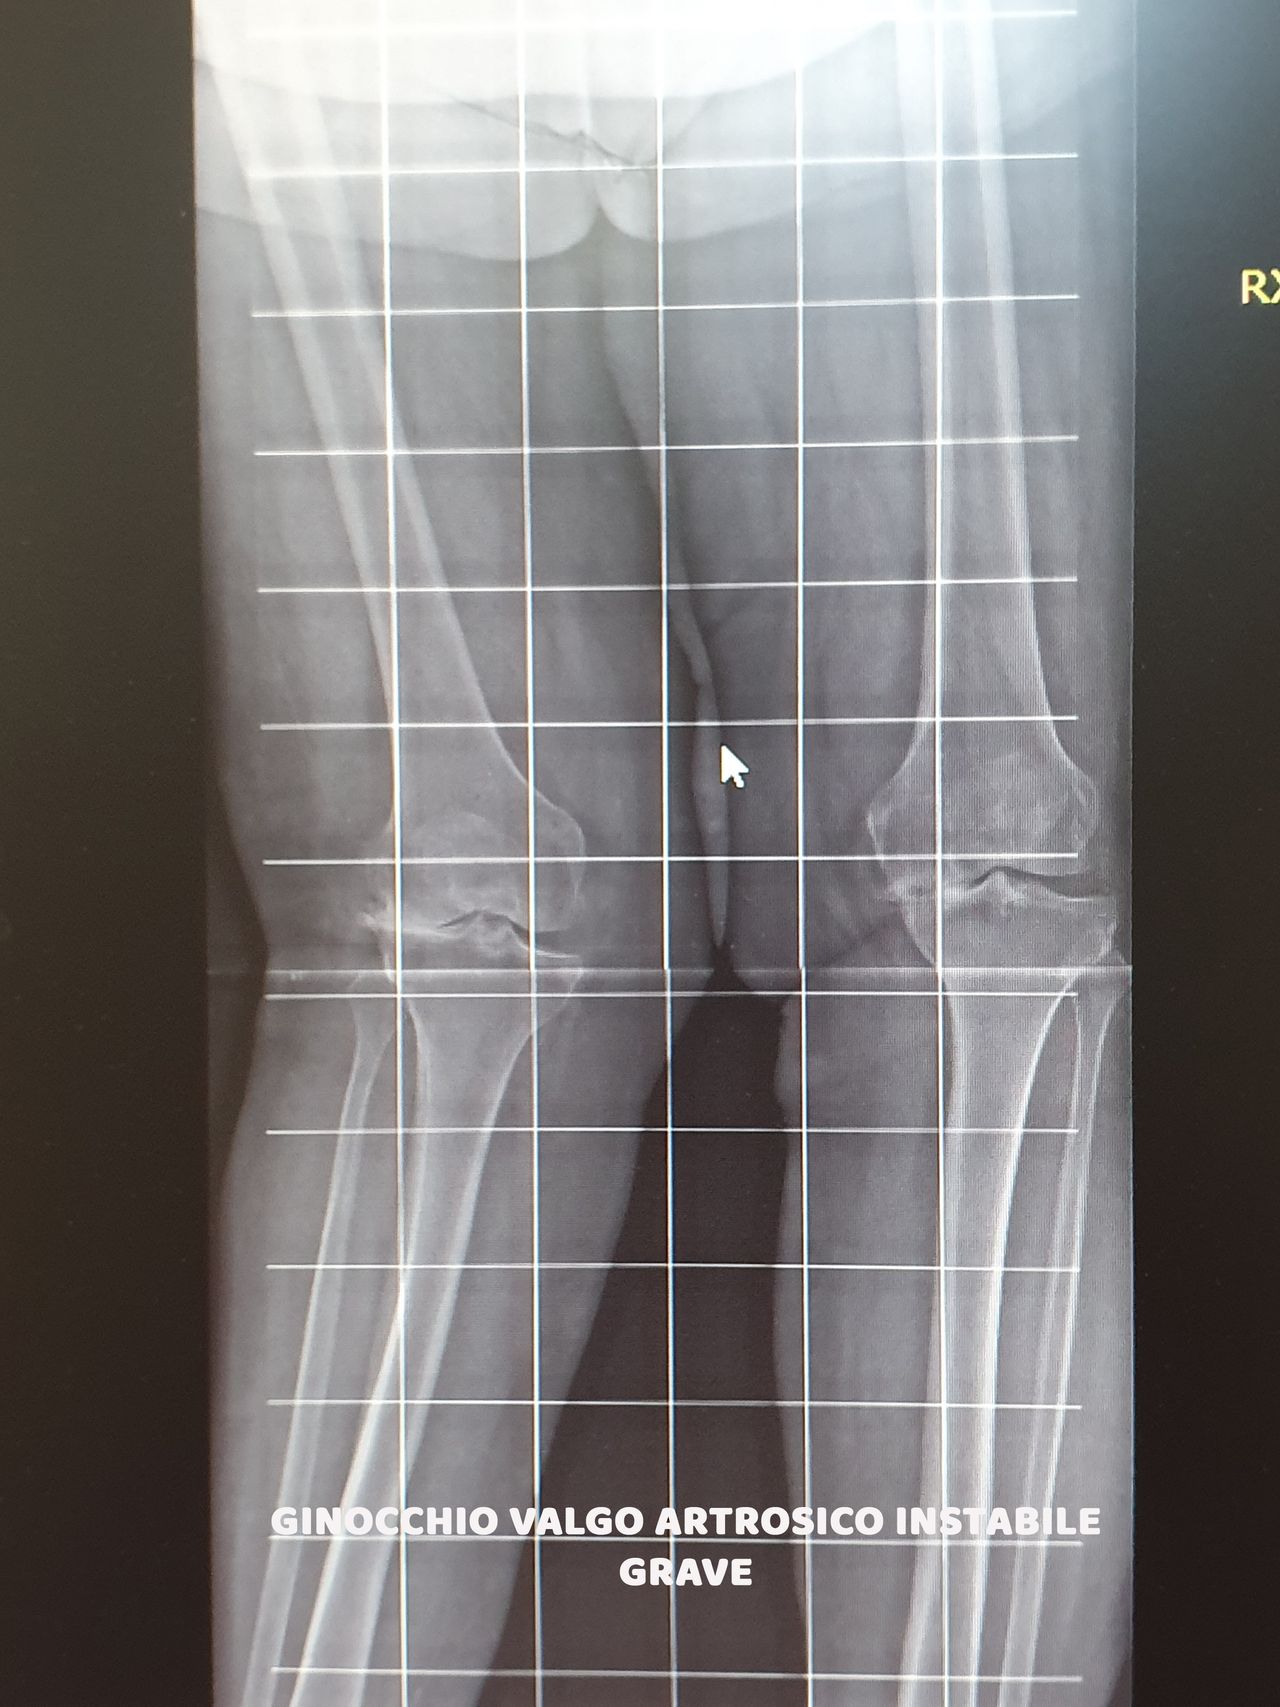

* Protesi Totali di Ginocchio, (ANALLERGICHE in Oxinium)

* Protesi Mono-Compartimentali di Ginocchio (ANALLERGICHE in Oxinium)